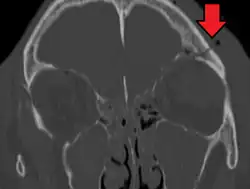

A subtle temporal bone fracture as seen on a CT scan

A basilar skull fracture as seen on CT